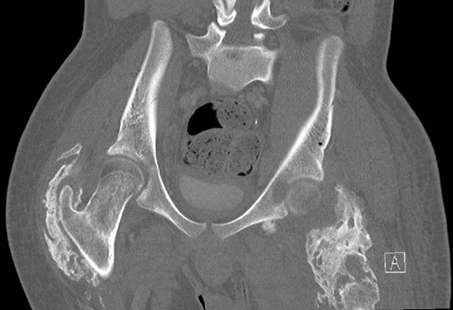

Figure 2.

Pelvic CT. CT in coronal view similarly depicted heterotopic ossification

involving bilateral hip joints.

(ROM). A pelvic X-ray and pelvic CT were therefore performed (Figure 1 and Figure 2). The pelvic

severe heterotopic ossification (HO). The pelvic CT (Figure 2) in coronal view similarly depicted heterotopic

ossification involving bilateral hip joints.